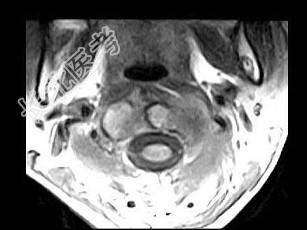

- 单项选择题女,29岁, 有午后发热,夜间盗汗, 消瘦等,枕颈部疼痛, 活动头部时加重,休息后减轻, 结合所提供的图像,最可能的诊断是 ( )

D、寰枢椎结核